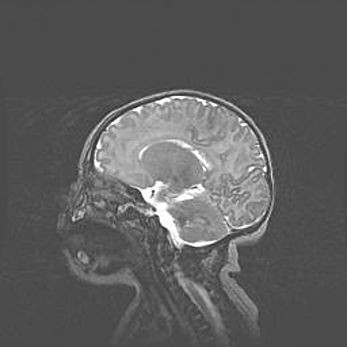

Открытая гидроцефалия.

Возраст: 9 месяцев 12 дней

Вес: 6800 г

Пол: мужской

Окружность головы: 41,5 см

Срок гестации: 28 недель

Гидроцефалия головного мозга у новорожденных имеет характерный признак: опережающий рост окружности головы приводит к визуально хорошо определяемой гидроцефальной форме сильно увеличенного в объёме черепа. Детские неврологи определяют следующие симптомы гидроцефалии у грудничков: выбухающий напряжённый родничок, частое запрокидывание головы, смещение глазных яблок к низу.